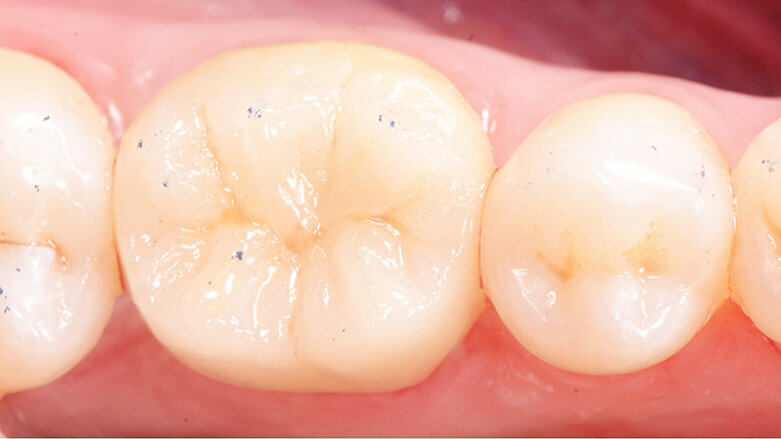

Fig. 1: Preoperative situation

A 45-year-old male patient presented to the practice with a restoration on tooth 46. The tooth had been endodontically treated and was temporized with a filling (Fig. 1). The temporary was removed, the tooth built up with Tetric N-Ceram Bulk Fill and then prepared for the crown restoration (Fig. 2). An impression was taken with a one-step two-phase impression technique using putty and light-body silicone. After scanning the model, the crown was designed in the software suite (inLab, Dentsply Sirona) and milled from an IPS e.max® lithium disilicate block (Fig. 3). After the crystallization firing the crown was stained and glazed (Fig. 4).